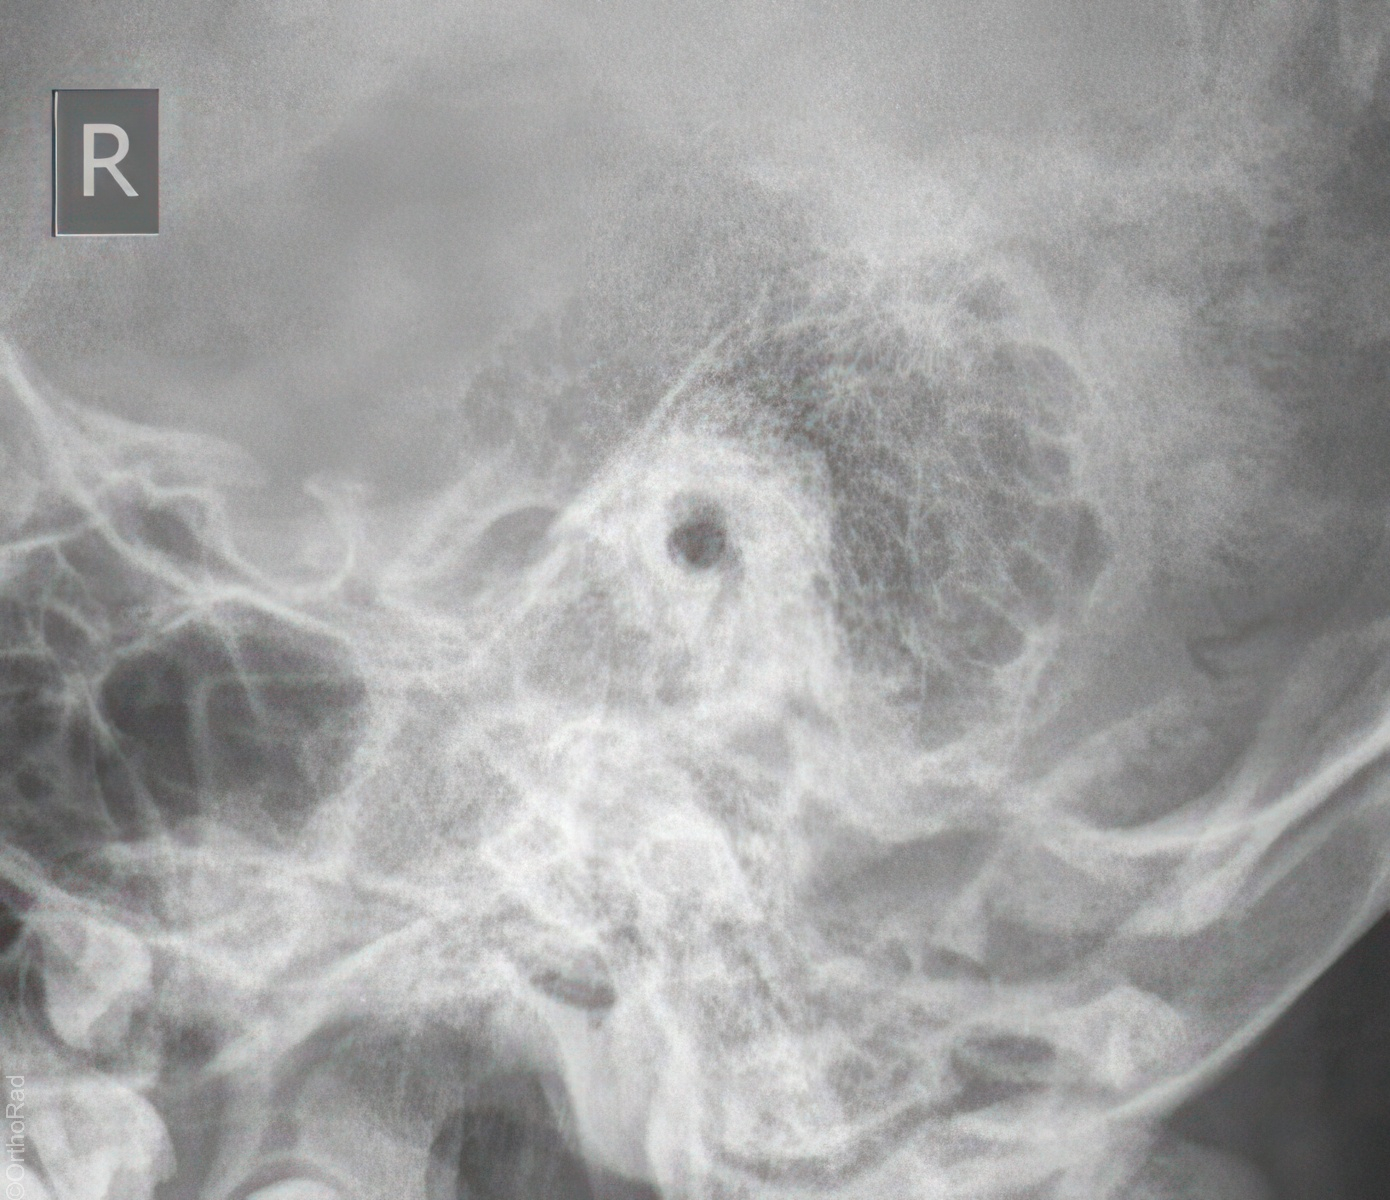

Schädel lateral

Fremdkörper-Lokalisation vor MRT, Shuntventil-Kontrolle

Vollständige Darstellung des gesamten Schädels, weitgehend deckend der Konturen, vordere und hintere Schädelgrube, Orbita, Kieferhöhlen und Jochbein. Zudem deckungsgleich von kleiner Keilbeinflügel und äußerer Gehörgang. Strichförmige Abbildung der Sella turcica.